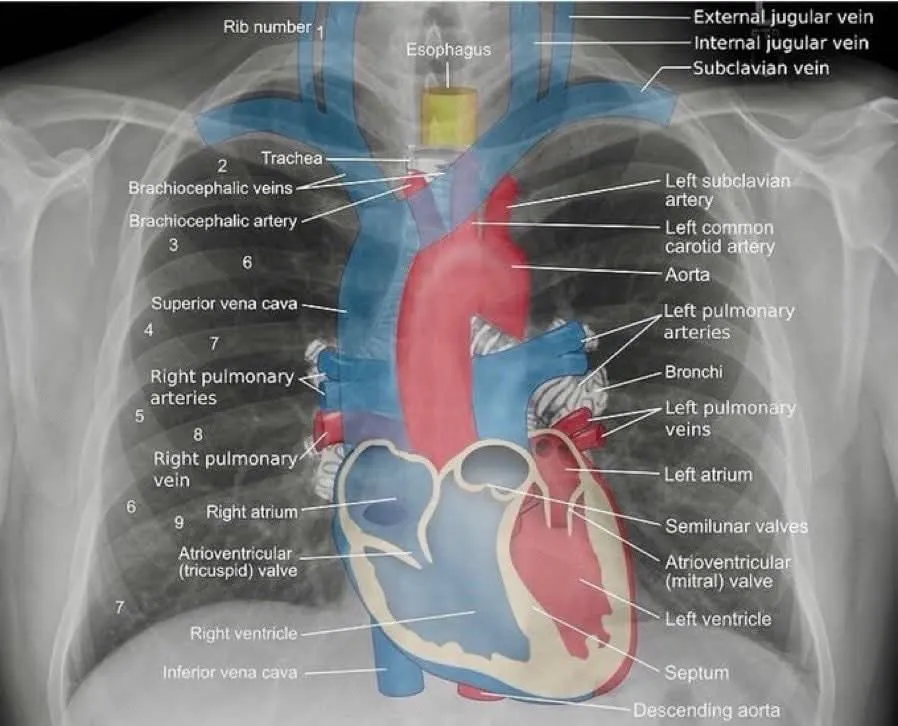

Chest X-Ray